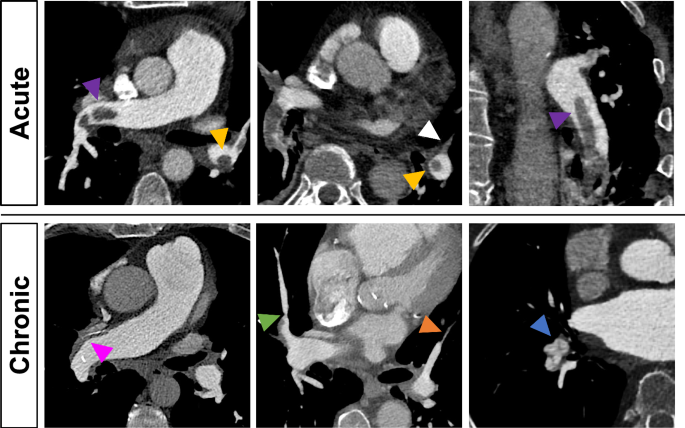

A radiologist with 4 years of experience in cardiovascular imaging (R.J.G.) assessed imaging findings indicating PE and CTEPH in accordance with the prevailing evidence available at the time the study was designed [9,10,11, 17]. These included: thrombus morphology/direct vascular features (e.g., “polo-mint” or “railway” sign, laminated thrombus), indirect vascular features (e.g., MPA dilatation, dilatated bronchial arteries), indirect cardiac features (e.g., right-ventricular (RV) dilatation or hypertrophy) and indirect parenchymal features (e.g., pulmonary infarction). Figure 1 illustrates typical examples of acute and chronic thromboembolic imaging features. All morphological imaging features are listed in Table 1.

Comparison of thromboembolic imaging features between acute and chronic PE. Acute PE: Central or eccentric filling defects surrounded by high-attenuation contrast medium (“polo-mint sign”—yellow arrowheads and “railway sign”—purple arrowheads) and complete arterial occlusion without lumen retraction (white arrowhead). Chronic PE: Laminated thrombus with calcifications (pink arrowhead), post-stenotic dilatation (green arrowhead), vascular retraction (orange arrowhead), and intravascular webs (blue arrowhead)